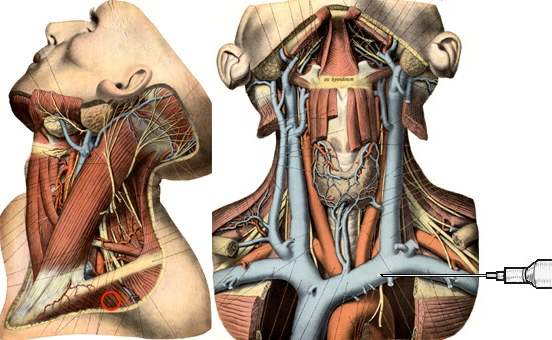

Die Vena jugularis/ Vena anonyma kann nach Yoffa zwischen medialem und lateralem Kopf des Musculus sternocleidomastoideus von ventral punktiert werden oder horizontal von lateral. Diese Methode wurde 1972 von den amerikanischen Herzchirurgen Garcia, Mispireta und Pinho nach ausführlichen anatomischen Präparationen als einfachster und ungefährlichster Zugang beschrieben. Das Zielgebiet, der Zusammenfluß von Vena jugularis und Vena subclavia zur Vena anonyma ist so groß, dass die Punktion auch ohne Sonographie immer beim ersten Stich gelingt.

Die Punktion von ventral kann unter realtime Sonographie mit einem Standardschallkopf wegen des geringen Abstands zur Clavicula nur in der kurzen Schallachse erfolgen, wobei die Nadel nur abschnittsweise sichtbar ist. Mit dem kleinen 22 MHz Fingerschallkopf aus der Rheumatologie ist auch eine Punktion in der langen Schallachse möglich.

Die in der Anästhesie verbreitete Punktion der distalen Vena jugularis ist komplikationsträchtig und sollte vermieden werden. Normalerweise liegt die Vena jugularis lateral der A. carotis.

Bei der schädelnahen Punktion muß der Kopf nach links gedreht werden, weil sonst das Kinn im Weg ist. Dadurch rotiert die Vene vor die Arterie und das Lumen wird schlitzförmig.

Vor der Einmündung in die Vena anonyma macht die Jugularvene einen Knick von 45 Grad nach dorsal. Diatator, Einführschleuse und Katheter stoßen dort an der Venenvorderwand an und erzeugen Intimaläsionen, die bei 30% der Patienten später zur Thrombose führen.

Darüberhinaus geht der Katheter durch die ganze Breite des Musculus sternocleidomastoideus. Dies führt zu einer rein/raus-Bewegung des Katheters bei jedem Schlucken und jeder Kopfbewegung. Das begünstigt einerseits das Einwandern von Hautkeimen in den Punktionskanal, andererseits werden Fibrinablagerungen auf der Katheteroberfläche an der Punktionsstelle abgestreift. Dadurch kommt es zu einer Akkumulation von Fibrin und thrombotischem Material an der Venenwand und um den Katheter.